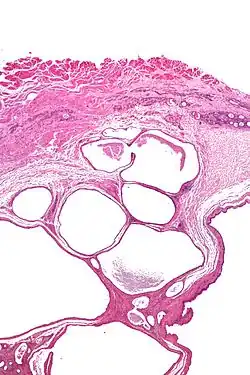

Micrograph of a cystic tumour of the atrioventricular nodal region. H&E stain. | |

Cystic tumours of the atrioventricular nodal region, true to their name, have cystic spaces, which are lined by a single layer of histomorphologically benign epithelial cells. The appearance is similar to that of lymphangioma and this is a name that has been used for this tumour.[1]